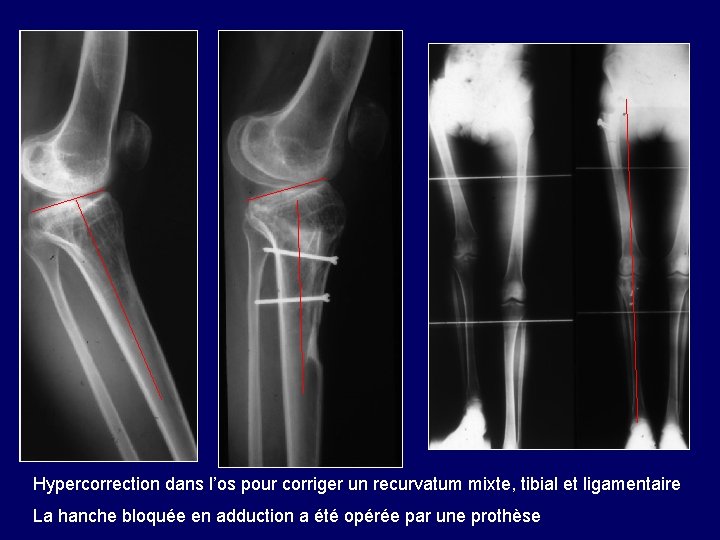

Recurvatum à la suite d’une longue immobilisation en plâtre dans l’enfance, pour une coxalgie Ce recurvatum mixte, osseux et ligamentaire, devra être hypercorrigé

Hypercorrection dans l’os pour corriger un recurvatum mixte, tibial et ligamentaire La hanche bloquée en adduction a été opérée par une prothèse